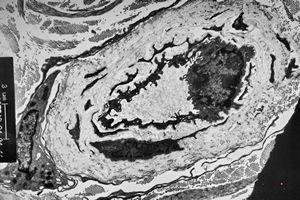

stabbed hypostom of the tick … toluidine-stained semithin section

stabbed hypostom of the tick … toluidine-stained semithin section (montage)